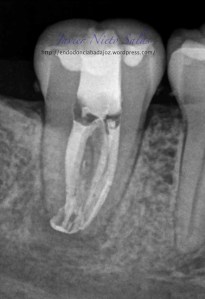

Se trata de una caso con una clasificación Tipo IIIb por el método de Min, ya pudimos sospechar que se trataba de un conducto en C:

Así podemos modificar nuestra técnica de obturación sabiendo que se trata de un sistema de conductos complicados

Con este par de casos quiero mostrar que  a todos nos sorprende, incluido yo,  la complejidad anatómica, pues nosotros SOLO conformamos, desinfectamos e intentamos obturar de la mejor manera, dejando la realidad del sistema de conductos en una interrogación a la que nos queremos acercar.